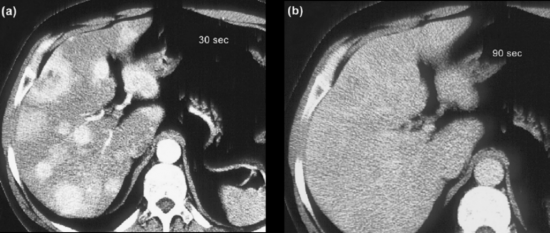

Exames de imagem são fundamentais para localizar o tumor primário, identificar sítios de doença metastática e avaliar a resposta ao tratamento, além de investigar a expressão de receptores de somatostatina. Tomografias (TC) e ressonâncias (RNM) são os métodos anatômicos mais empregados, mas cuidados técnicos são essenciais para otimizar a sensibilidade dos exames. A RNM é ligeiramente superior à TC, principalmente na avaliação do fígado e do pâncreas. Metástases hepáticas de TNE podem ser de difícil identificação à TC, uma vez que são comumente isodensas em relação ao fígado nas imagens de fase venosa portal (figura 1). Por esse motivo, a realização de exame trifásico é recomendada (VAN ESSEN, 2014). A avaliação de resposta por RECISTtem limitações em TNE, assim como em outras neoplasias em que agentes biológicos citostáticos são parte importante do tratamento. Apesar disso, os critérios RECIST seguem sendo utilizados nos maiores estudos clínicos de TNE.

Figura 1.

TC de abdome em paciente com tumor neuroendócrino com metástases hepáticas após 30 segundos (a) e 90 segundos (b) da injeção do meio de contraste. O realce das lesões desaparece na fase venosa. Adaptado de Rockall e Reznek, 2007.